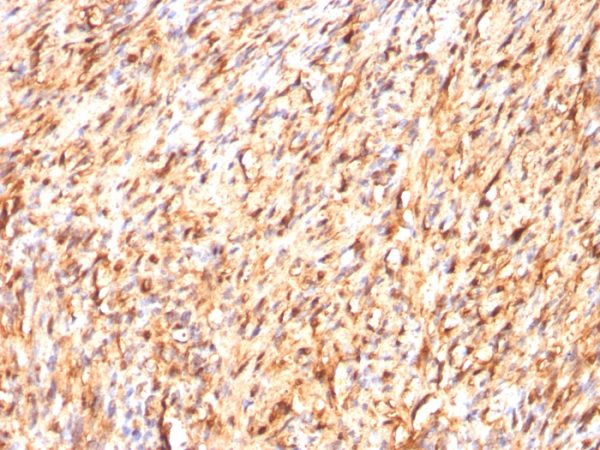

Immunohistochemistry (IHC)

1-2ug/ml

30 min at RT. Staining of formalin-fixed tissues requires heating tissue sections in 10mM Tris with 1mM EDTA, pH 9.0, for 45 min at 95°C followed by cooling at RT for 20 minutes

The specificity of this monoclonal antibody to its intended target was validated by HuProtTM Array, containing more than 19,000, full-length human proteins. S100 belongs to the family of calcium binding proteins. S100A and S100B proteins are two members of the S100 family. S100A is composed of an alpha and a beta chain whereas S100B is composed of two beta chains. This antibody is specific against an epitope located on the beta-chain (i.e. in S-100A and S-100B) but not on the alpha-chain of S-100 (i.e. in S-100A and S100A0). This antibody can be used to localize S-100A and S-100B in various tissue sections. S-100 protein has been found in normal melanocytes, Langerhans cells, histiocytes, chondrocytes, lipocytes, skeletal and cardiac muscle, Schwann cells, epithelial and myoepithelial cells of the breast, salivary and sweat glands, as well as in glial cells. Neoplasms derived from these cells also express S-100 protein, albeit non-uniformly. A large number of well-differentiated tumors of the salivary gland, adipose and cartilaginous tissue, and Schwann cell-derived tumors express S-100 protein. Almost all malignant melanomas and cases of histiocytosis X are positive for S-100 protein.

Human brain or melanoma. A2058 or SK-N-MC cells.